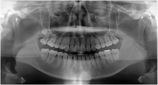

健康な小臼歯を抜いていません

矯正前                 矯正後

治療前 の レントゲン です 動く矢印治療後 の 歯列レントゲン です